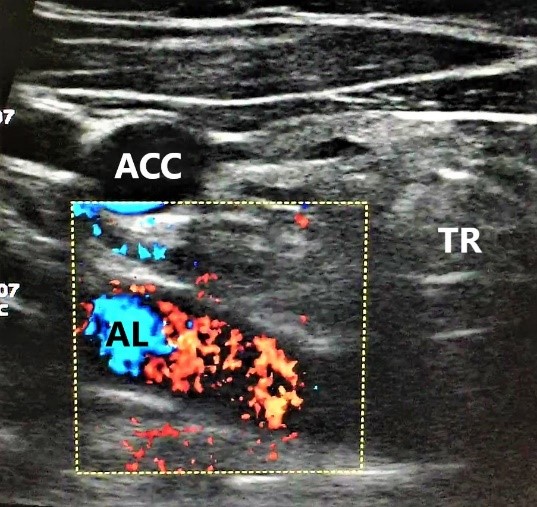

- На уровне правого грудино-ключичного сочленения AL и правая общая сонная артерия располагаются отдаленно друг от друга. Данная сонографическая картина выявлена у всех 4 пациенток (рис. 3).

Рис. 3. Пациентка 58 лет, ИМТ – 21,7. а – цветное дуплексное сканирование сосудистого пучка правой половины шеи линейным датчиком на уровне правого грудино-ключичного сочленения. Правая общая сонная артерия прослежена до места “пересечения” с трахеей (БЦС не выявлен). AL располагается на значительном расстоянии от правой общей сонной артерии. б – интраоперационная картина. НВГН I типа (по Avisse–Toniato) имеет нисходящее направление и состоит из двух веток (стрелки). в – аксиальный КТ-скан с ангиографией сосудов дуги аорты. AL располагается позади трахеи и пищевода. г – компьютерная трехмерная реконструкция демонстрирует синтопию AL с общей сонной артерией. AL является последней, четвертой ветвью дуги аорты. ACC – arteria carotis communis dexter, TR – trachea, E – esophagus. VJI – vena jugularis interna dexter, NV – nervus vagus dexter.

Рис. 4. Пациентка 68 лет, ИМТ – 31,6. а – УЗИ сосудистого пучка правой половины шеи линейным датчиком в В-режиме. б – цветное дуплексное сканирование сосудистого пучка правой половины шеи линейным датчиком. AL расположена параллельно плоскости сканирования. Правая общая сонная артерия и трахея находятся перпендикулярно относительно датчика. в – интраоперационная картина. Мобилизована правая доля ЩЖ, отведена медиально. НВГН состоит из двух веток (стрелки). г – интраоперационная картина. Выполнена тиреоидэктомия. НВГН IIA типа (по Avisse–Toniato) имеет горизонтальный ход. д – аксиальный КТ-скан с ангиографией сосудов дуги аорты. AL располагается позади трахеи и пищевода. е – компьютерная трехмерная реконструкция демонстрирует синтопию AL с общей сонной артерией. AL является последней, четвертой ветвью дуги аорты. ACC – arteria carotis communis dexter, TR – trachea, E – esophagus.

Этапы операции менялись при выявлении характерных сонографических черт для AL. Опасаясь повреждения НВГН, мобилизация ЩЖ начиналась с боковой поверхности доли с прецизионным выделением всех структур, особенно зоны верхнего полюса. В трех случаях НВГН имел горизонтальный ход (НВГН IIA типа по Avisse–Toniato), а в одном – нисходящее направление (НВГН I типа по Avisse–Toniato). Также нами отмечено изменение топографии структур правого сосудисто-нервного пучка шеи. Во всех случаях блуждающий нерв располагался кзади и медиальнее правой общей сонной артерии в непосредственной близости к хирургическим манипуляциям и легко идентифицировался при незначительной тракции правой общей сонной артерии (рис. 3).